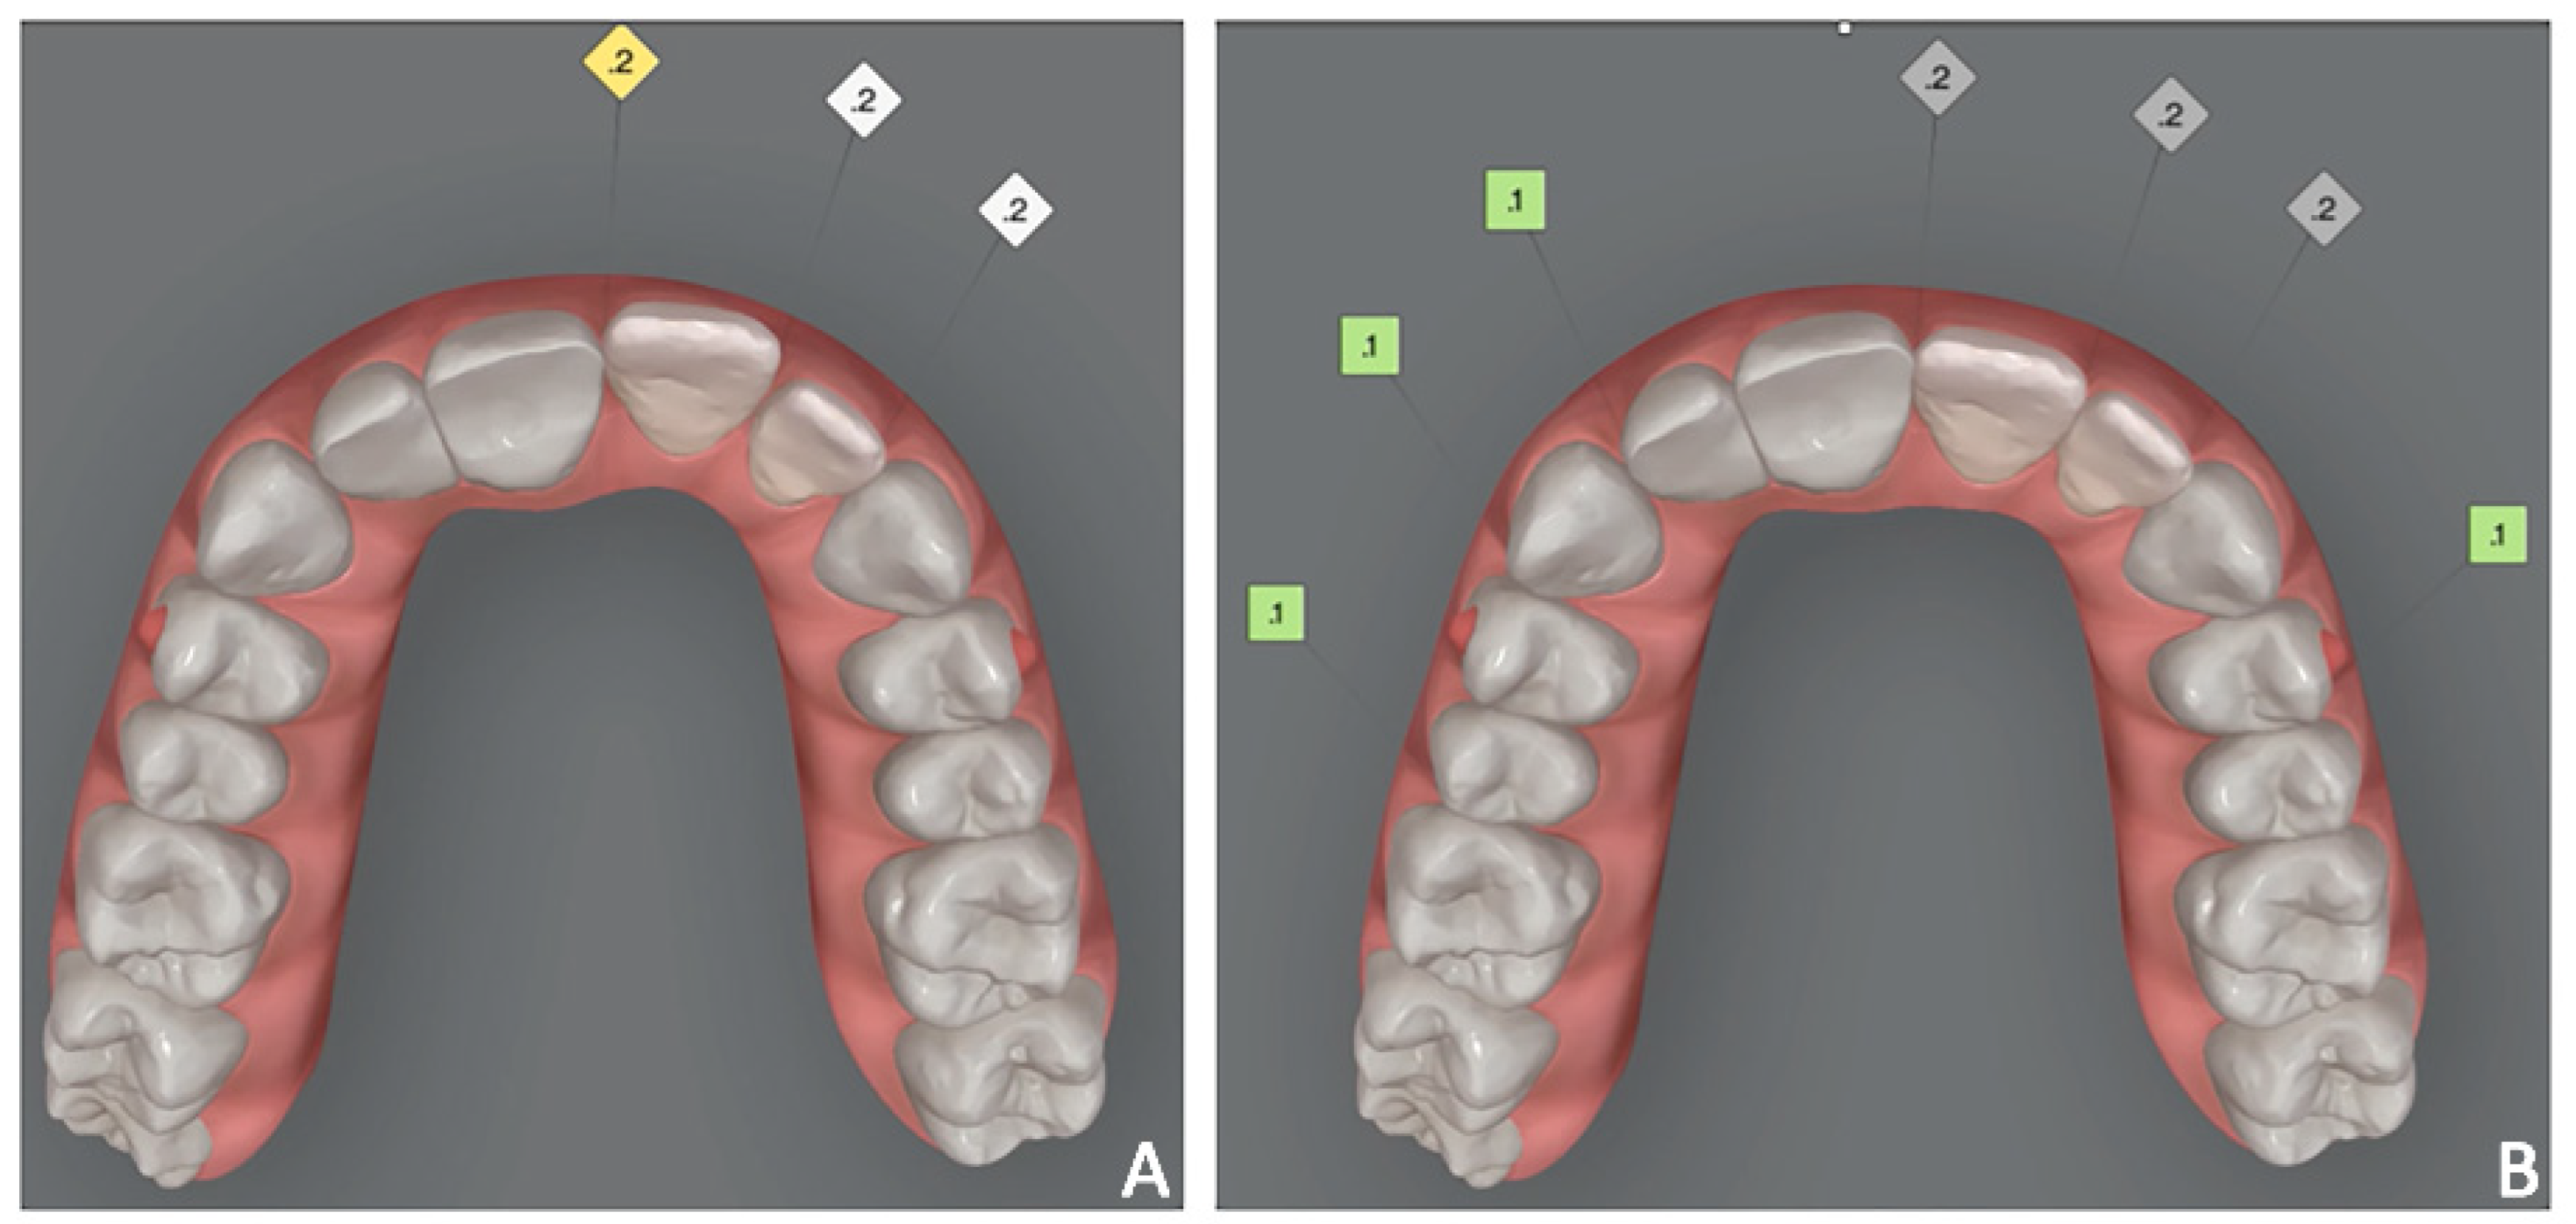

Figure 18. Case 3. (A) Orthodontic set-up (Invisalign Go platform); (B) intra-oral photograph with clear aligner.

Orthodontic set-up. The orthodontic treatment aimed to optimize the position of the anterior teeth for the final prosthetic rehabilitation. In particular, the treatment plan involved the reduction of incisors flaring and diastemas to correct incisal guidance and better support prosthetic crowns and smile aesthetics. The programmed orthodontic movement was staged, and eight aligners were required to achieve the final pre-prosthetic teeth position. The patient wore each aligner for two weeks for a total treatment time of 4 months (Figure 18A,B).

4.